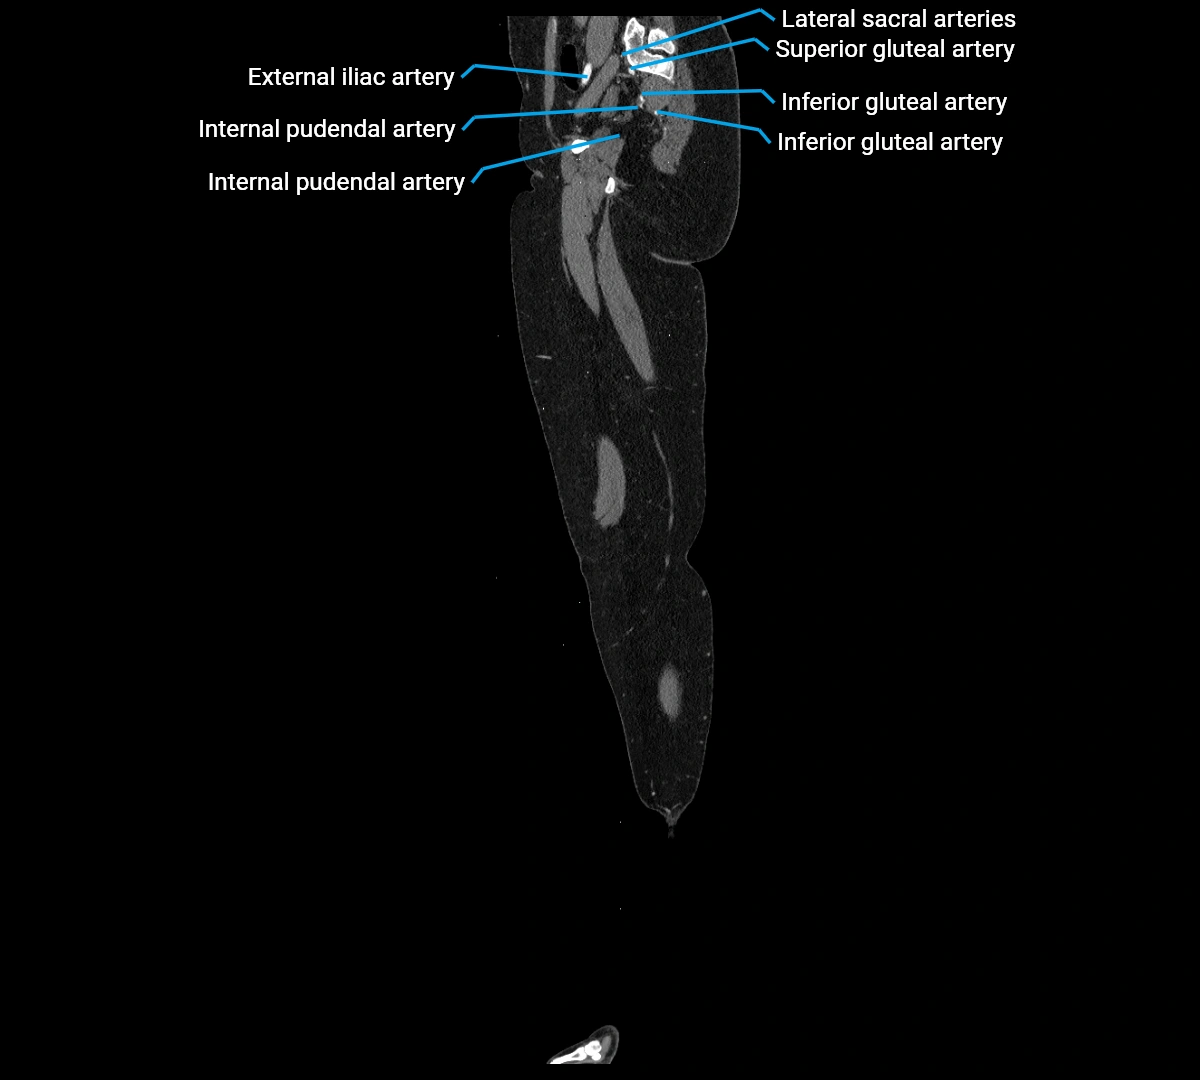

CT images

image